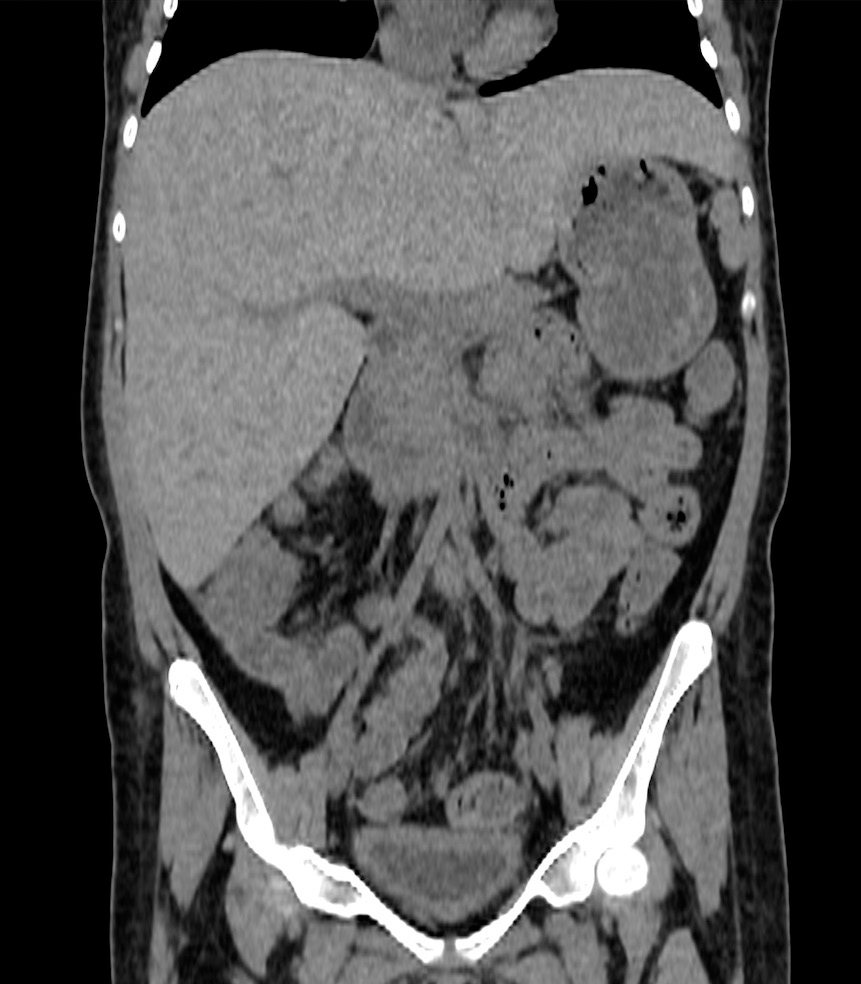

Tomografía computada (TAC) sin contraste que evidencia moderada hepatomegalia de 18 cm en su eje longitudinal (Figura 1).

Figura 1: Corte coronal de escáner sin contraste.